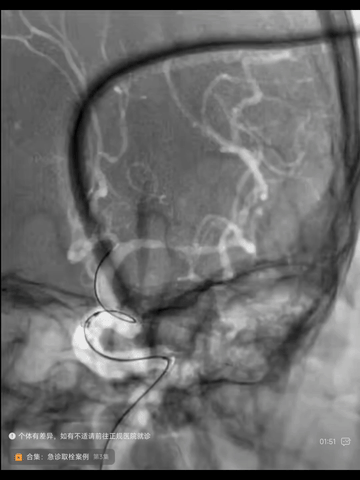

造影见左MCA主干狭窄临近下干开口,下干起始部合并中度狭窄。0.014"synchro导丝导引微导管进入左MCA M2分支,撤出synchro导丝,送入300cm Transend导丝后,交换出微导管。

经微导丝送入2*10mm球囊(赛诺),其过虹吸段困难,推高中间管和长鞘增强支撑后,球囊顺利进入颅腔,以6atm压力扩张左MCA狭窄病变,球扩后顺势把中间换头端推送到ICA末端。

球扩后造影示下干起始部狭窄加重,并在短时内趋于闭塞,考虑是主干球扩后斑块位移累及下干开口所致。